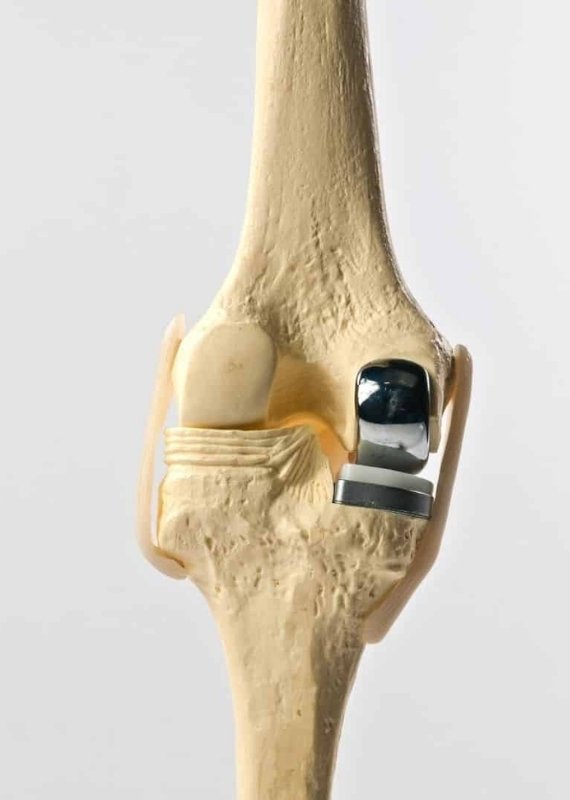

Partial Knee Replacement in Ahmedabad (also known as unicompartmental knee arthroplasty) is a surgical procedure where only the damaged portion of the knee joint is replaced with a prosthetic implant. This allows the healthy parts of the knee, including the ligaments and surrounding bone, to remain untouched, preserving more of your natural joint structure and movement.

Unlike a Total Knee Replacement, this procedure targets specific damage caused by localized arthritis or injury, making it less invasive and offering a quicker recovery with a more natural knee feel.

Only the damaged knee compartment is resurfaced

Preserves healthy bone, tissue, and ligaments